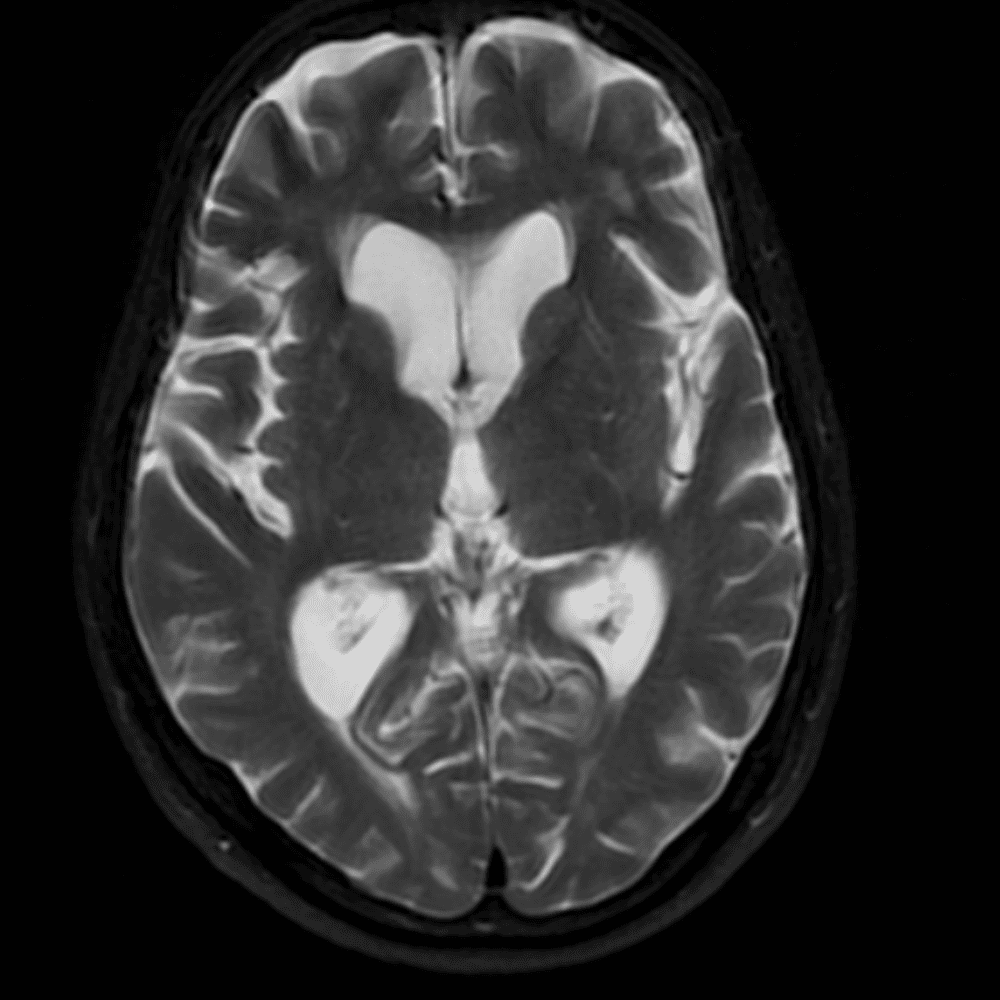

๋‹น์ง ์‹œ ํ”ํžˆ ๋ณผ ์ˆ˜ ์žˆ๋Š” ์‚ฌ๋ก€์˜ ์ „ํ˜•์ ์ธ ์˜ˆ๋ฅผ ํฌํ•จํ•ฉ๋‹ˆ๋‹ค.

39 ์‚ฌ๋ก€

์—ฐ์Šต

๋ฏธ๋ฌ˜ํ•˜๊ฑฐ๋‚˜ ์–ด๋ ค์šด ์‚ฌ๋ก€์™€ ์ผ๋ถ€ ์ •์ƒ ์‚ฌ๋ก€๋ฅผ ํฌํ•จํ•˜์—ฌ ๋‹น์ง์„ ์‹œ๋ฎฌ๋ ˆ์ด์…˜ํ•ฉ๋‹ˆ๋‹ค.

50 ์‚ฌ๋ก€